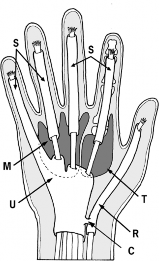

The "thumb-in-palm" deformity is a complex, multi-planar contracture frequently encountered in patients with upper motor neuron lesions, such as cerebral palsy, traumatic brain injury, or cerebrovascular accidents. This debilitating posture severely compromises hand function, negating the ability to perform pinch, grasp, or release maneuvers. The deformity is primarily driven by the spastic overactivity of the adductor pollicis, flexor pollicis brevis (FPB), and flexor pollicis longus (FPL), coupled with the relative weakness or flaccidity of the abductor pollicis longus (APL), extensor pollicis brevis (EPB), and extensor pollicis longus (EPL).

The Smith FPL abductorplasty is a profound biomechanical alteration designed to eliminate the deforming volar-ulnar force of a spastic FPL and convert it into a powerful radial abductor. By rerouting the FPL tendon to the dorsoradial aspect of the metacarpophalangeal (MCP) joint, the tendon's moment arm is shifted, augmenting thumb abduction while simultaneously mitigating the flexion-adduction contracture.

While the Smith procedure addresses the volar deforming forces, the Manske technique focuses on optimizing the dorsal extensor mechanics. In the normal hand, the EPL tendon (residing in the third dorsal compartment) acts as an adductor and extensor of the thumb. In the spastic hand, this adduction vector exacerbates the thumb-in-palm deformity.

By surgically releasing the EPL from the third compartment and redirecting it through the first dorsal compartment, its vector is shifted radially. The EPL is transformed from an adductor-extensor into a pure abductor-extensor, providing a powerful dynamic force to pull the thumb out of the palm.